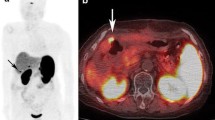

Similar pathological tumor sites were visible on both 68Ga-DOTA-NOC and OCT in a total of 41 regions in all 19 patients. Additional foci of pathological uptake were seen in 21 regions on 68Ga-DOTA-NOC only and in 15 regions on OCT only. Foci of tracer uptake were observed in the liver, pancreas, bone, lymph nodes, digestive tract, as well as a few additional findings in other parts of the body including soft tissue, brain, thyroid, and tonsils. Differences between the two imaging modalities did not appear to be more prevalent in specific regions (see Table 3). 68Ga-DOTA-NOC uptake in tumor foci was often very intense, and this is reflected in the maximum SUV which ranged from 2 to 165 (see Table 2). As seen from Tables 2 and 3, many findings were comparable in both imaging modalities, though even in those regions where identical tumor foci were described, foci of enhanced tracer uptake were generally clearer on the 68Ga-DOTA-NOC images, and with the assistance of co-registered CT for all scans, anatomical localization of findings was easier and more precise. Examples of images showing comparable findings in both modalities, but illustrating greater clarity and contrast with 68Ga-DOTA-NOC, are shown in Figs. 1 and 2.

Patient 19: a PET 68Ga-DOTA-NOC maximum intensity projection showing two distinct foci of enhanced activity in the liver (thin arrow) and in two retroperitoneal nodes (thick arrow). b Whole body planar OCT image (anterior view) showing the same two foci in the liver (thin arrow). The retroperitoneal nodes are not visualized here; these nodes were also not visible on the posterior view (not shown).

Patient 19: a Transaxial PET 68Ga-DOTA-NOC image showing the two foci in the liver (thin arrow) seen in Fig. 1. b Corresponding CT image. c Transaxial SPECT OCT image showing the same two foci in the liver (thin arrow). d Corresponding CT image. Note the lack of complete correspondence between the slices on the two modalities due primarily to difference in patient position (arms up for the PET, arms down for the SPECT); difference in CT images is also due to respiration during prolonged CT acquisition on SPECT/CT.

An example of tumor foci seen only on 68Ga-DOTA-NOC, with no corresponding foci on OCT, is shown in Fig. 3 where intense uptake is clearly seen in a pre-aortic lymph node on 68Ga-DOTA-NOC, while no corresponding abnormality is visible on OCT. Additional findings on 68Ga-DOTA-NOC included a site of primary tumor in the tail of the pancreas in the case of a patient with MEN1; this tumor, shown in Fig. 4, was not identified on OCT. In contrast, Fig. 5 shows an example of findings on OCT that were not seen on 68Ga-DOTA-NOC; however, apart from this example and one other, all the remaining 13 findings seen only on OCT were faint and described as suspicious areas rather than well-defined tumor foci, such as in Fig. 5.

Patient 19: a Transaxial PET 68Ga-DOTA-NOC image showing one of the two retroperitoneal nodes (thin arrow) seen in Fig. 1. b Corresponding CT image. c Transaxial SPECT OCT image, like the planar image, fails to demonstrate this node. d Corresponding CT image.